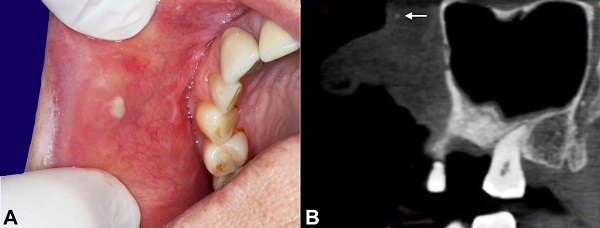

A 63-year-old woman presented to the oral and maxillofacial department complaining of a painful suppurative lesion on the buccal mucosa for several days. The patient reported several episodes of asymptomatic, non-suppurative swelling in the same lesion area over the last 15 years. The patient’s medical history was unremarkable. Intraoral examination revealed a painful nodular swelling of the buccal mucosa with mucopurulent discharge (Figure 1A). The computed tomography finding (Figure 1B) was consistent with a small calcification in the buccal mucosa. After antibiotic treatment, an excisional biopsy was performed.